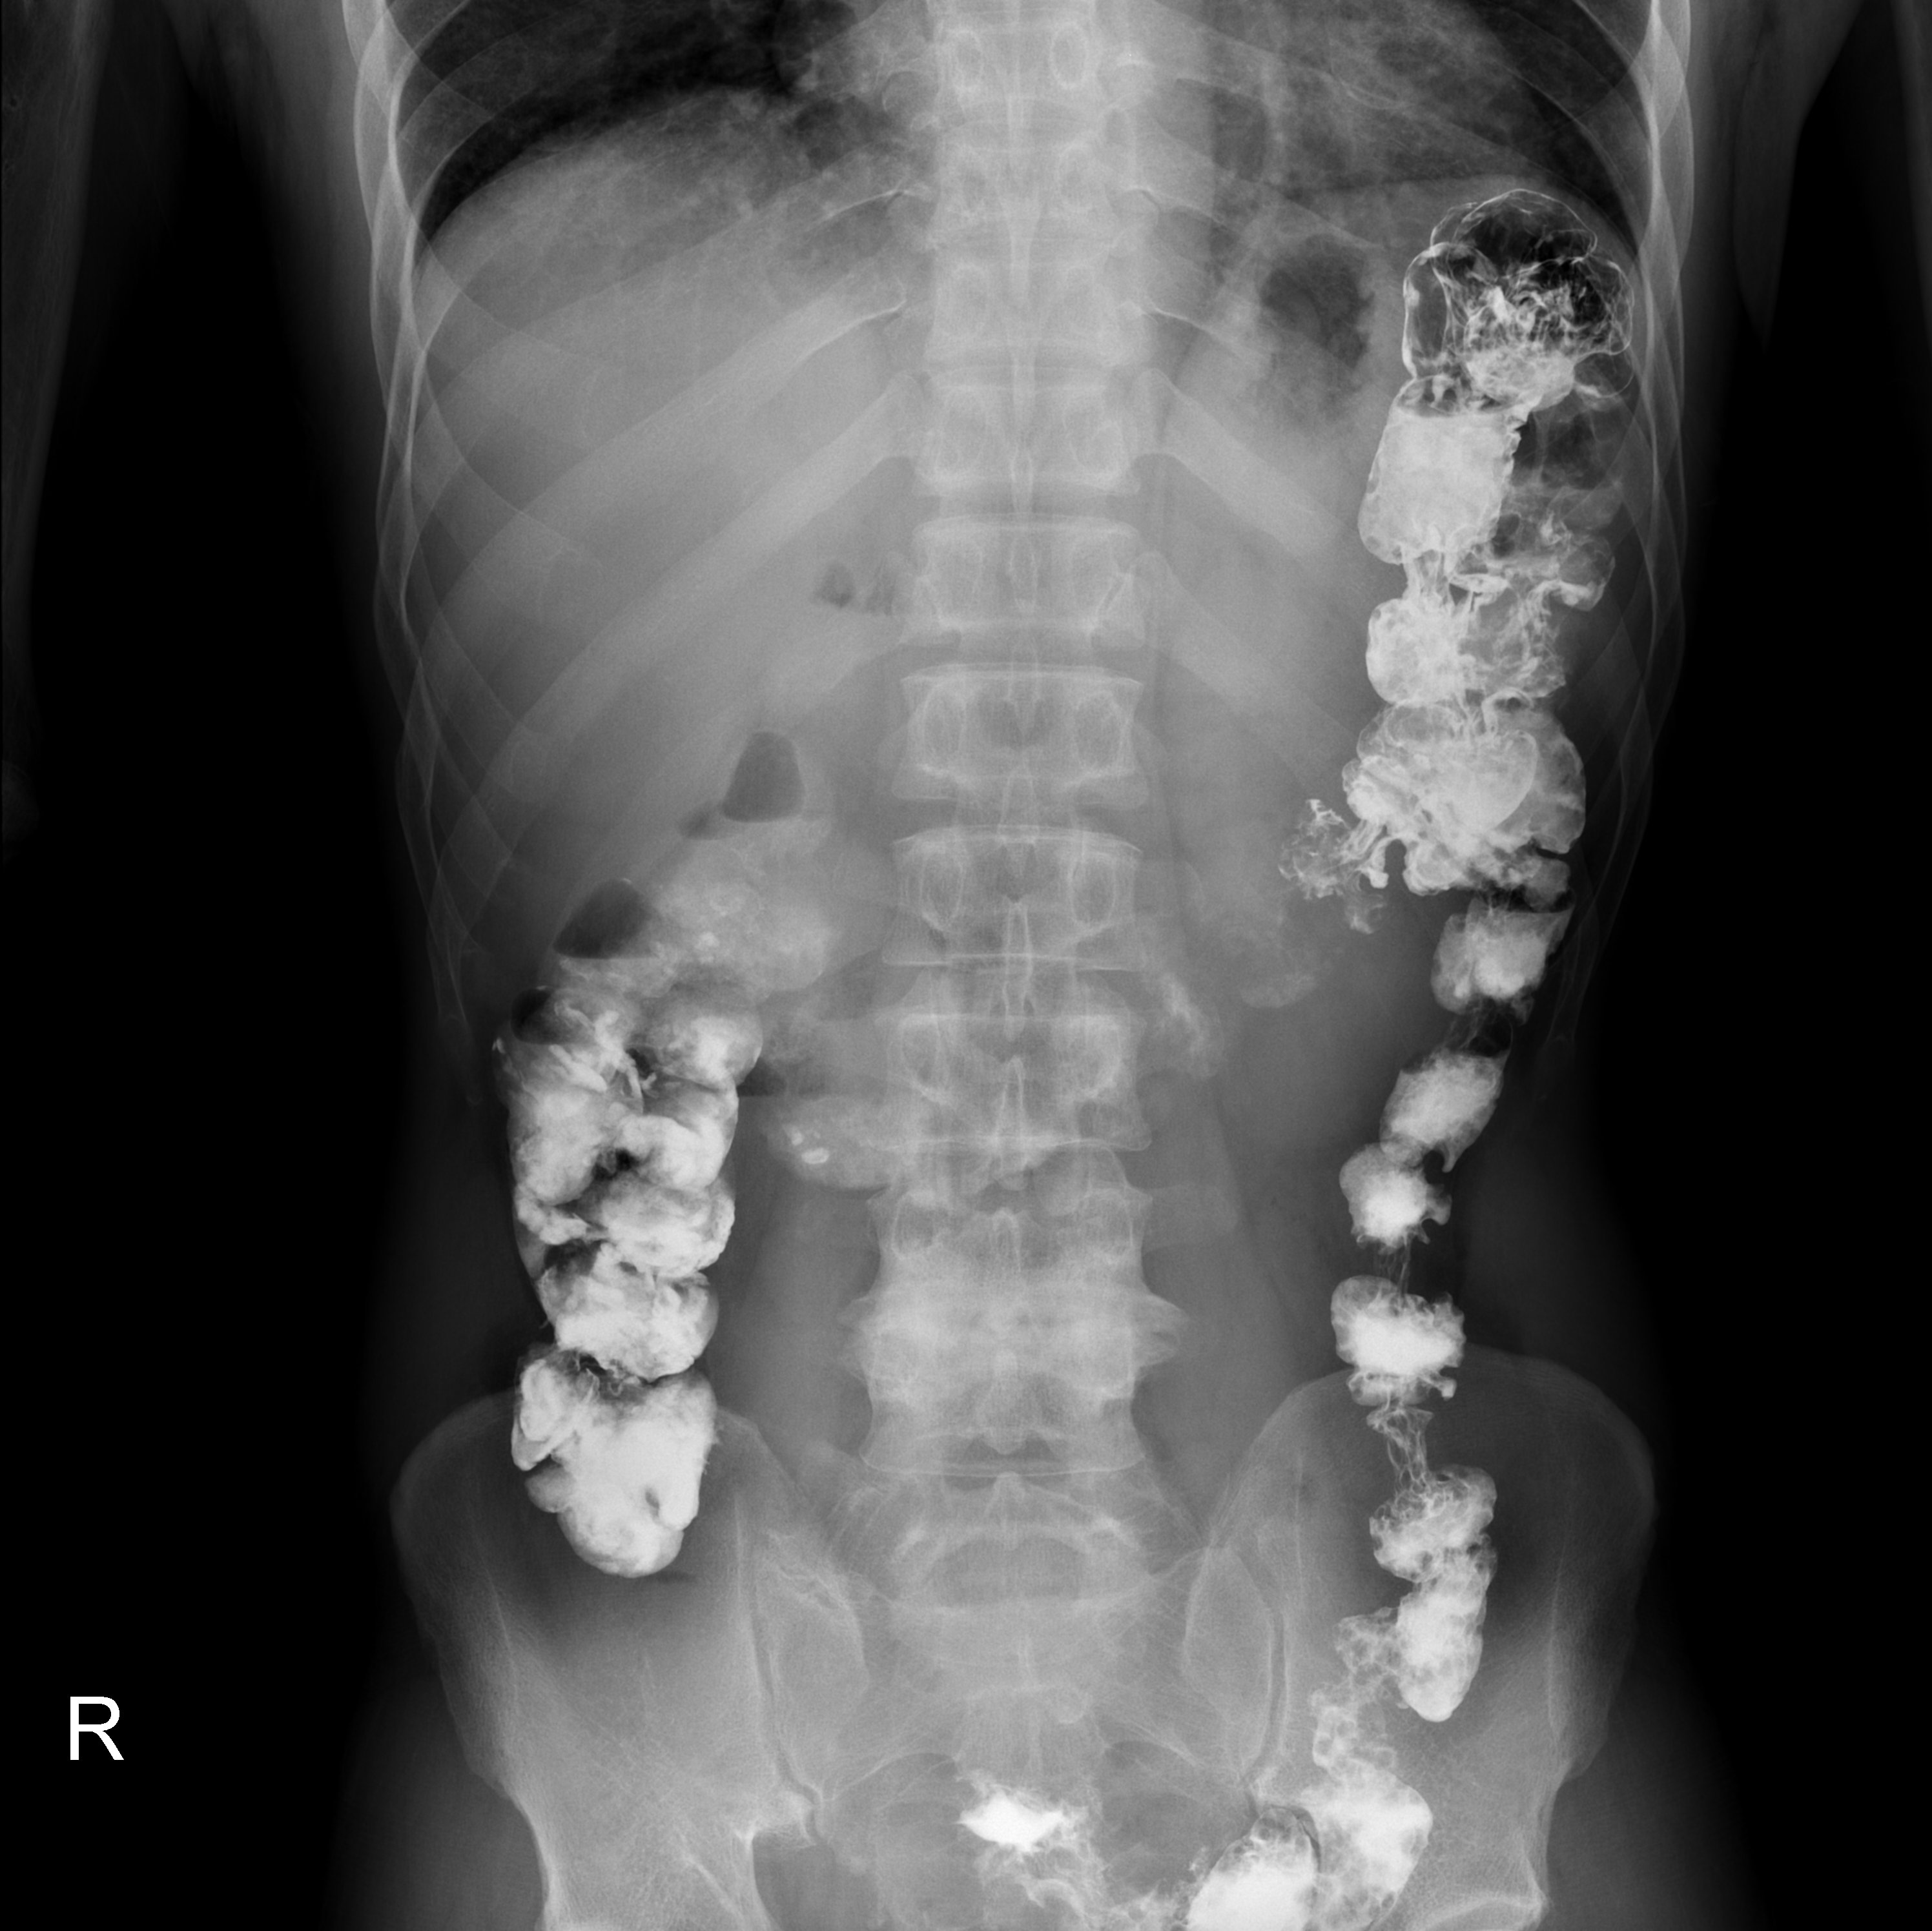

Ну, что ж, рисну, пожалуй. Образование справа, на мой взгляд, исходит из верхнего полюса правой почки, и извне прорастает печень. Хотя по реконструкциям все не так однозначно. Но реконструкции некачественные из-за толстых срезов (" ...танцору сцена мала"(с)

) Кроме этого - нарушение уродинамики справа до ср/3 мочеточника. Причина для меня не вполне ясна, конкремента явно не вижу, может быть и опухоль. Не хватает экскреторной фазы, обычно мы делаем не через 3 (как здесь), а через 10 минут, при необходимости совсем отсроченно - 2-3 часа. Про толстую кишку не скажу, а вот стенки мочевого пузыря - совсем не нравятся, утолщены, с неровными, нечеткими контурами, плюс наличие дефектов наполнения.

КТ. Фиброламеллярный рак либо крупная аденома правой доли печени. Думаю, кроме биопсии, тут мало кто разберется.

Выраженный воспалительный процесс в малом тазу (проктит, сигмоидит, параректальный абсцесс кпереди от прямой кишки тоже не исключается, скорее такой мощный дивертикулитище - картинки похожи - http://translate.googleusercontent.com/translate_c?hl=ru&langpair=en%7Cru&rurl=translate.google.ru&twu=1&u=http://radiographics.rsna.org/content/20/2/399/F14.expansion.html&usg=ALkJrhik6KXUHBayN_8pOnUQlaim6nvLqw и http://translate.googleusercontent.com/translate_c?hl=ru&langpair=en%7Cru&rurl=translate.google.ru&twu=1&u=http://radiographics.rsna.org/content/20/2/399/F13.expansion.html&usg=ALkJrhibMhaoK8xWREOn2ZlXQ380ToAjiQ ).

Справа камень (а может, и два) в дистальной трети мочеточника.

Мочевой оценивать не берусь: нет тугого наполнения+перипроцесс, так что рекомендовала б УЗИ мочевого пузыря при нормальном тугом его заполнении, дальнейшая тактика от находки.

Рака почек не нашла.

По рентгенограммам легких патологии не нашла.